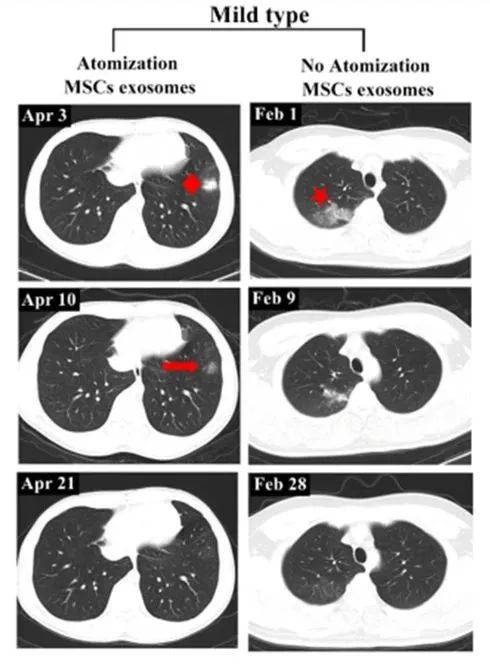

輕度病例前后影像變化:以患者 6 為例,2020 年 4 月 3 日,該患者第一次 CT 掃描顯示左肺下葉外有孤立結(jié)節(jié),4 月 4 日,患者接受外泌體霧化治療,4 月 10 日,第二次 CT 檢查顯示左肺下葉結(jié)節(jié)密度明顯降低,大小也縮小,4 月 21 日,第三次 CT 檢查,左下肺病灶完全吸收,從發(fā)現(xiàn)結(jié)節(jié)到完全吸收肺部病變所需的時間為 18 天。

相比之下,另一例患者(輕度病例,無霧化治療)類似肺部病變的吸收時間為 27 天。

左:患者 6;右:無外泌體霧化治療的輕度病例